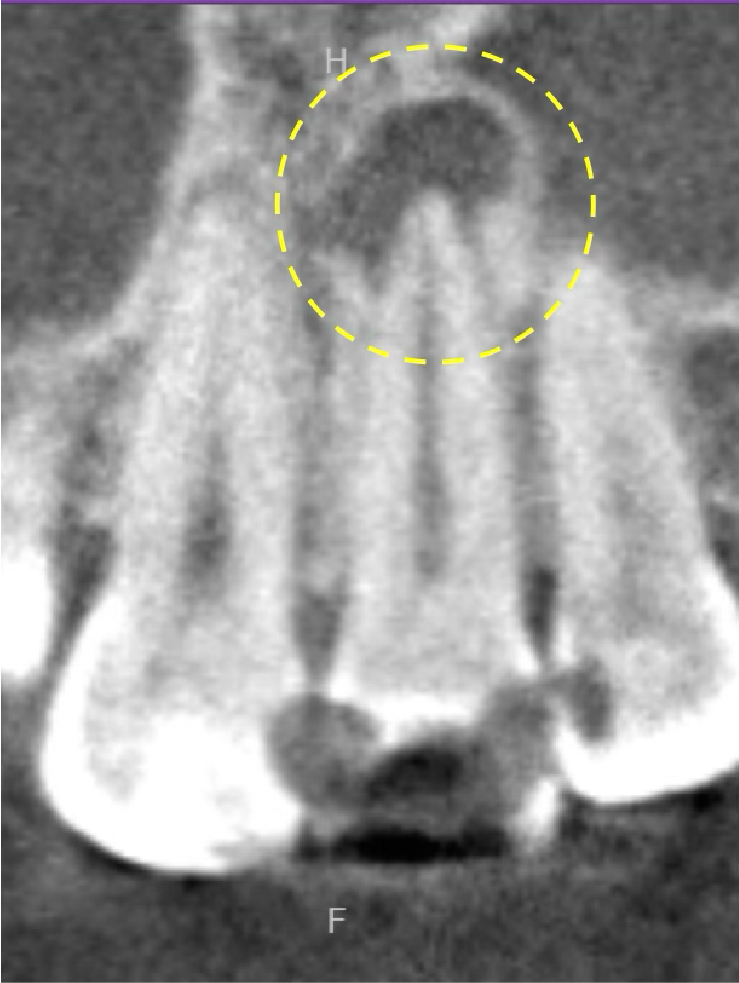

レントゲン・CT画像にて、右下第一大臼歯の根尖部に、明瞭な骨吸収像が認められます。来院時には根管治療の途中の状態でしたが、内部に虫歯が残っており、感染源が取り除けていない状態でした。急性炎症に対して確実な即効性がある治療はありませんが、最大限感染を除去し、細菌の侵入を防ぐことを第一に応急対応を行いました。

術後6ヶ月が経過時点でのレントゲン・CT画像では、もともとはっきりと写っていた根の先の黒い部分は消失し、骨の回復が認められます。痛みも全くなくなり、治癒していると判断し、最終補綴(かぶせもの)を行うことになりました。